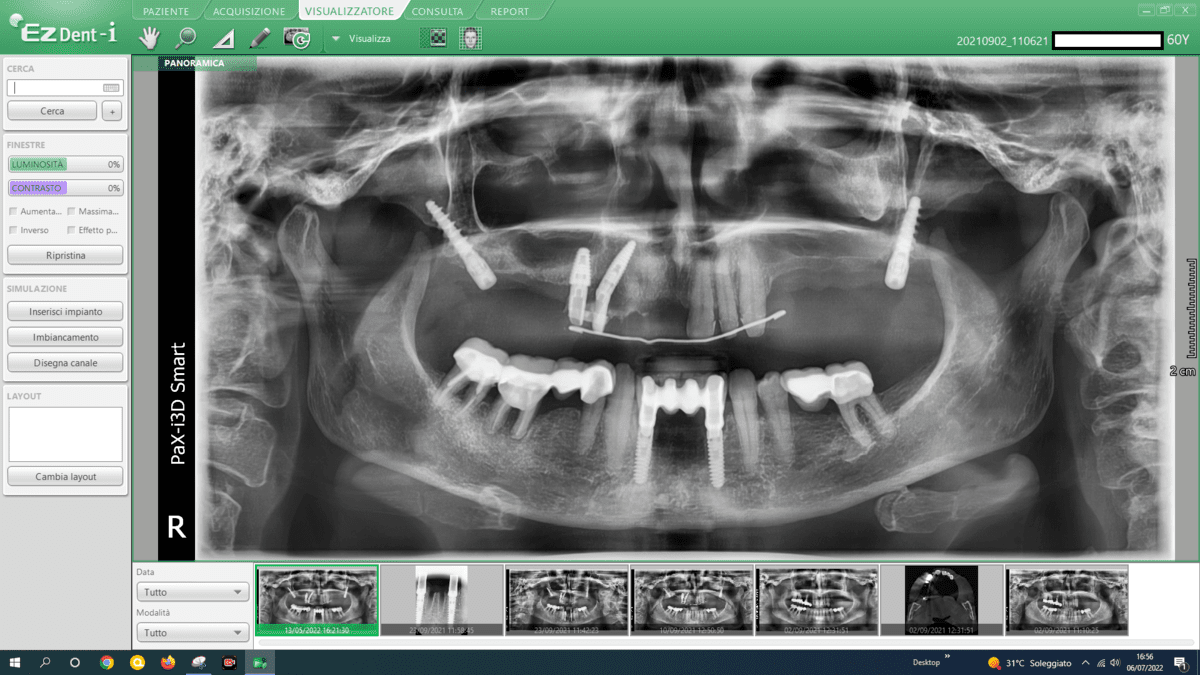

- Zygomatic Implants:

- At our center, we avoid this procedure thanks to Galileus Cerclage Sinus® surgery. If not possible, we also avoid it with the Pterygoid Zygomatic technique. Zygomatic implants are longer implants anchored to the zygomatic bone (cheekbone). They are used when the maxillary bone is severely atrophied, providing an alternative to bone grafts or sinus lift procedures.

- All-on-4 or All-on-6 Procedures:

- A more comprehensive surgery like Galileus Cerclage Sinus® would be more beneficial. These procedures involve placing a fixed prosthesis supported by four or six dental implants. The strategic placement of implants allows support for an entire arch of teeth, relying less on extensive bone support.

- Advanced Implant Techniques:

- Advanced implant techniques, such as Galileus Cerclage Sinus® mentioned in previous conversations, can offer innovative solutions for addressing atrophies. These techniques focus on strategically placing implants to optimize bone utilization.